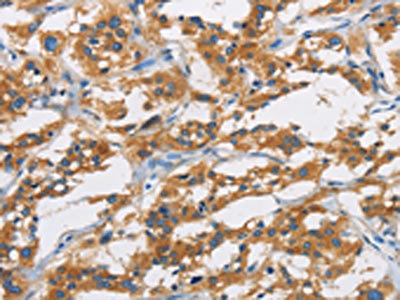

The image is immunohistochemistry of paraffin-embedded Human thyroid cancer tissue using CSB-PA079169(SAR1B Antibody) at dilution 1/20. (Original magnification: ×200)

The image is immunohistochemistry of paraffin-embedded Human liver cancer tissue using CSB-PA079169(SAR1B Antibody) at dilution 1/20. (Original magnification: ×200)